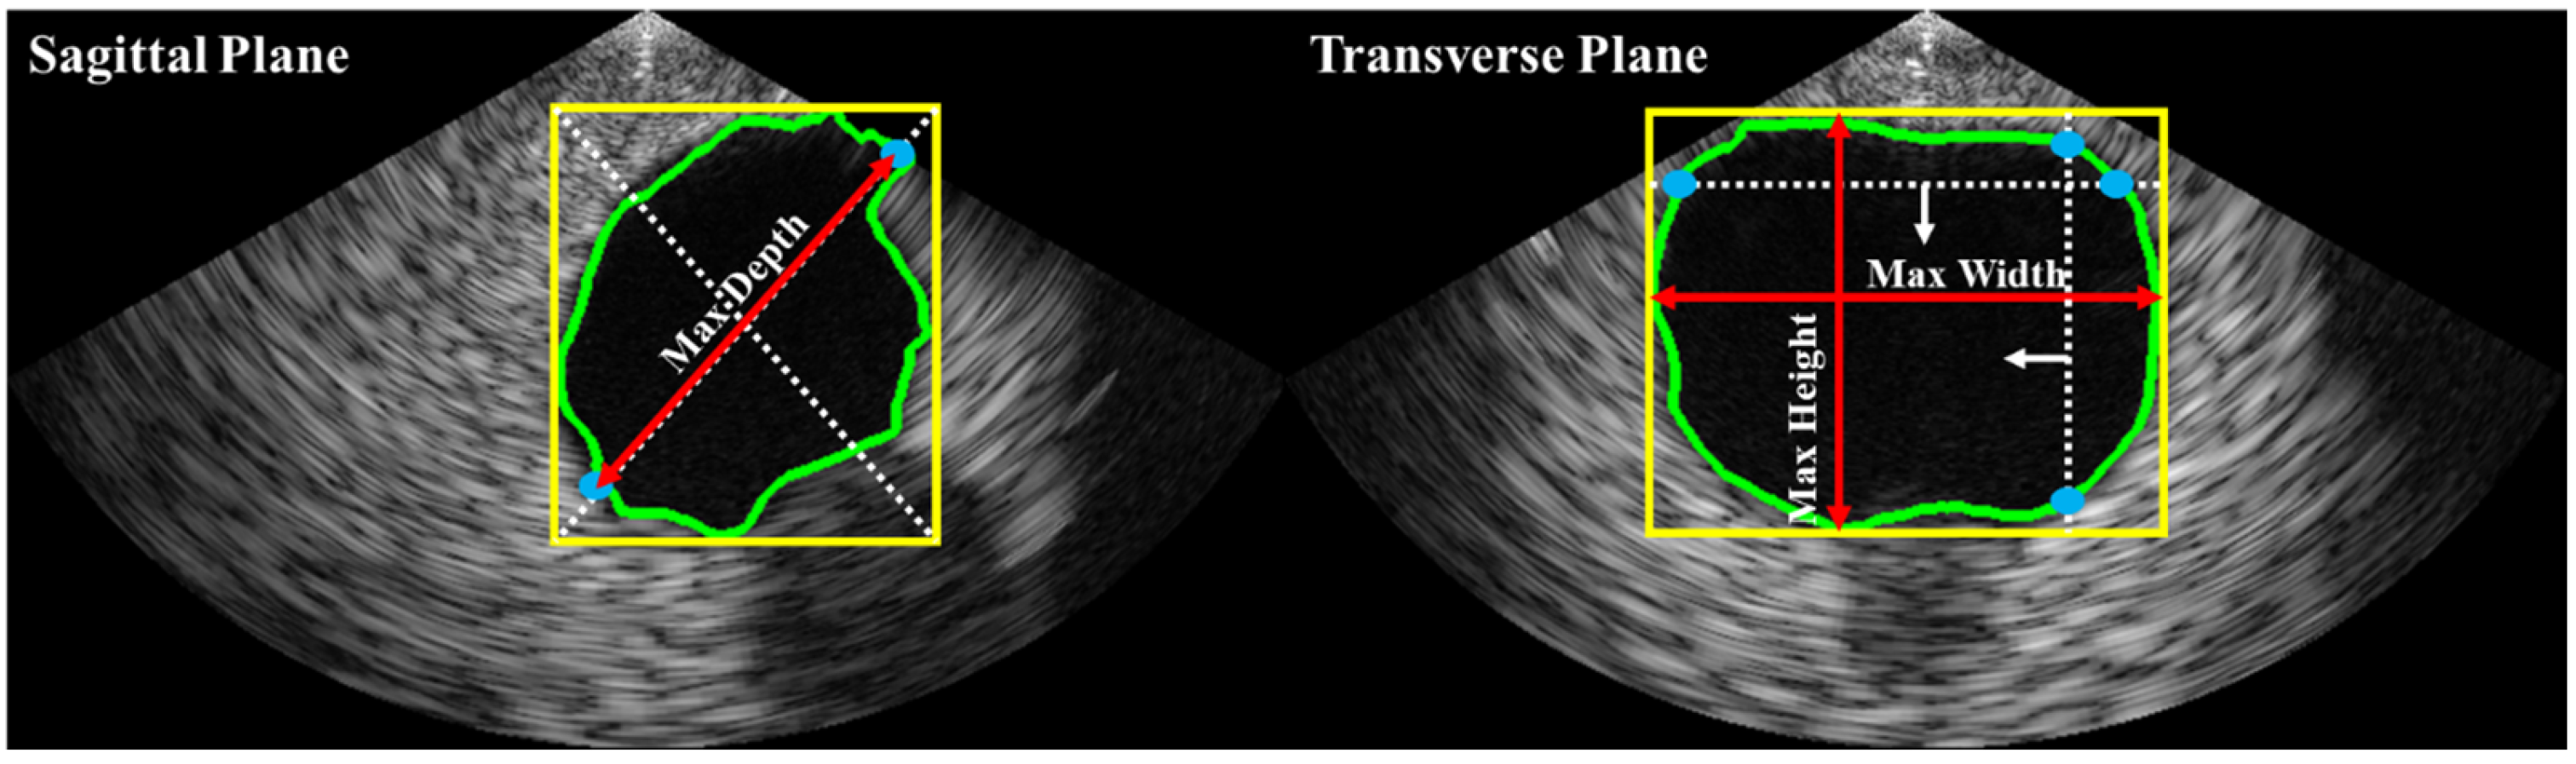

Bladder volume is typically estimated based on shape coefficients and measurements of height, width, and depth on two different planes (i.e., sagittal and transverse). In this study, as illustrated in Figure 4, depth was estimated on the sagittal plane, while height and width were estimated on the transverse plane. The bladder volume was then calculated using Equation (1), where c is a constant determined by the shape of the bladder region (e.g., 0.52 for a spherical shape, 0.7 for an unknown shape [21]).

Figure 4.

Automated axes detection for estimating bladder height, width, and depth from biplane ultrasound images. The bladder ROI dimensions were obtained by calculating the minimum enclosing bounding box (yellow line). In the sagittal plane, the greater distance between two intersections (blue dots) of the bounding box’s diagonal line (white dashed lines) with the bladder ROI contour (green line) was used to estimate depth. The red arrow lines represent the estimated depth. In the transverse plane, the maximum distances of the vertical and horizontal intersections were used to estimate height and width, respectively.